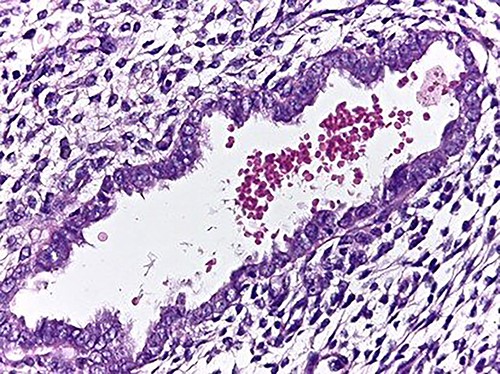

The microscopic study reported ileocolic intussusception and cecal endometriosis (Figs 4 and 5).

High magnification image (40x); endometrial gland and stroma without atypia. Erythrocytes within the lumen of the gland.